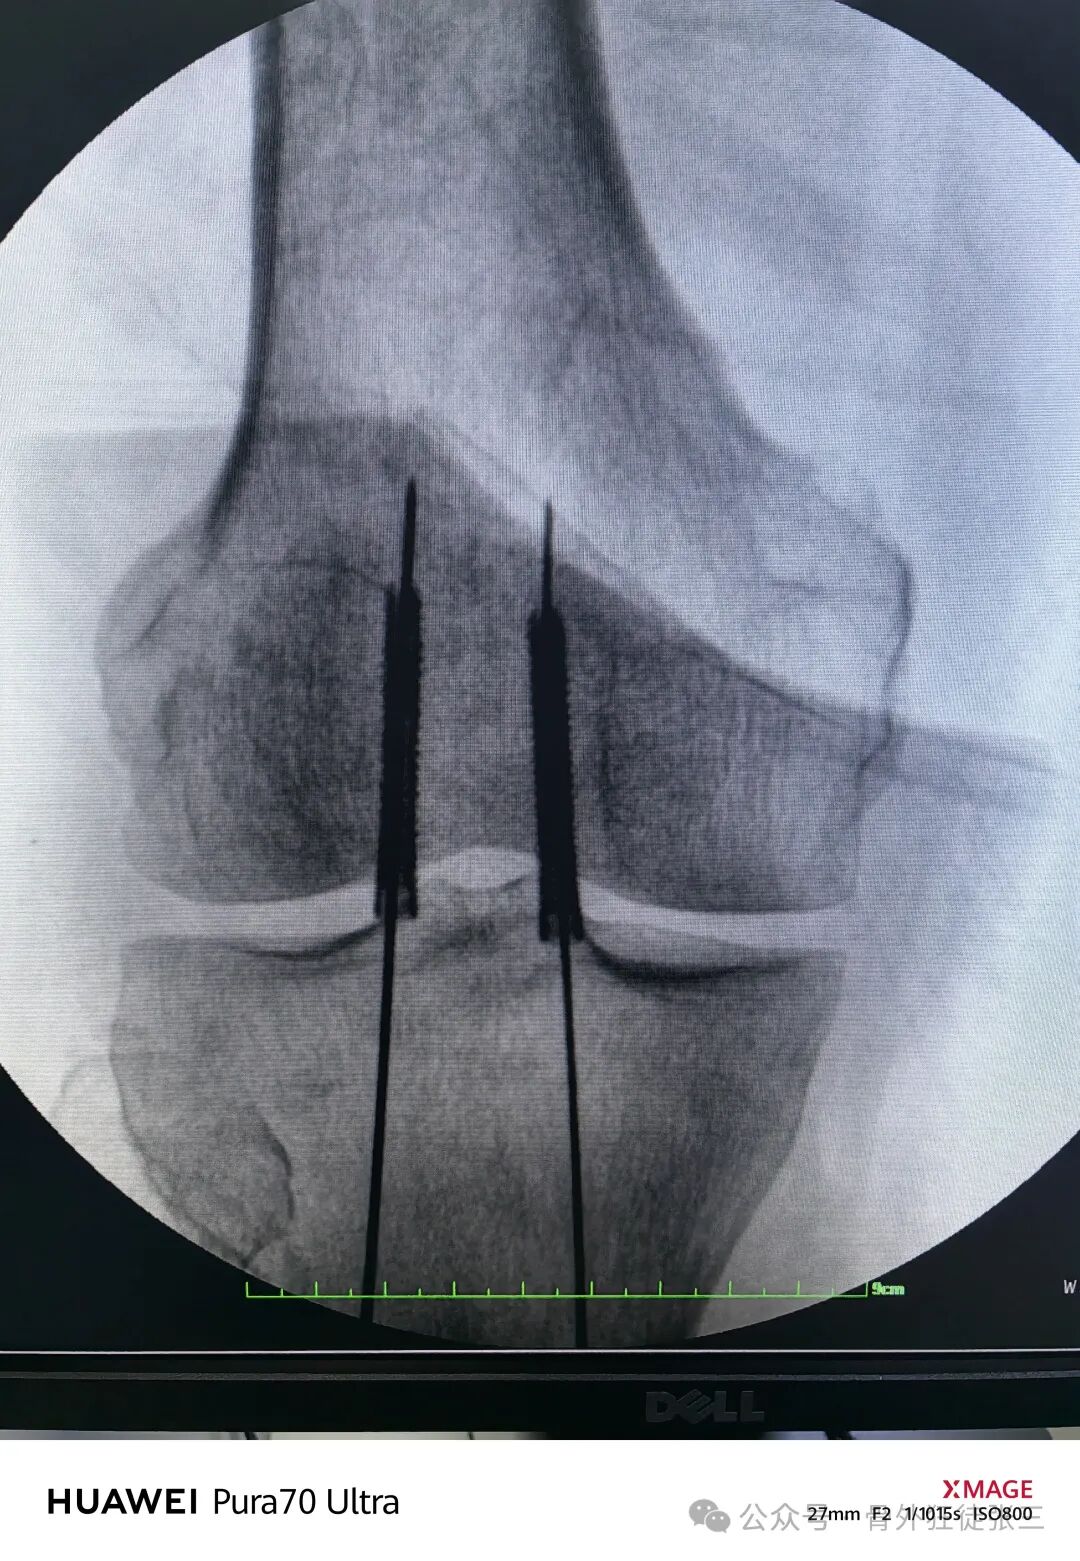

20ml注射器针头定位+当做导向器

-

1.2mm导针从针头导向器进入

透视正位侧

打导针